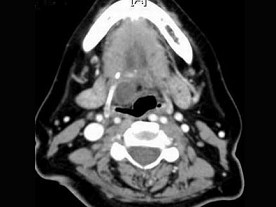

3.女,57岁,颈部不适,CT如图所示,应诊断为 ( )![]() ![]() ![]() ![]() |

| 正确答案:C |